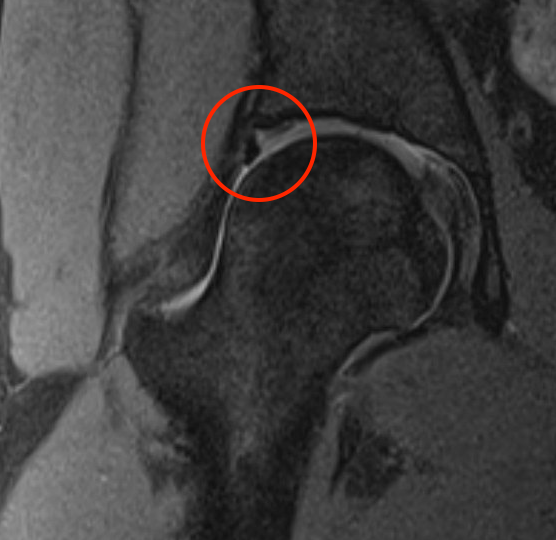

MRI

Labral tears

Best seen on coronal MRI

Saied et al BMC Musculoskeletal Disorders 2017

- systematic review

- labral tears: MRI sensitivity 86% and specificity 83%

- chondral lesions: MRI sensitivity 87% and specificity 72%

- labral tears: MRA sensitivity 91% and specificity 58%

- chondral lesions: MRA sensitivity 75% and specificity 79%